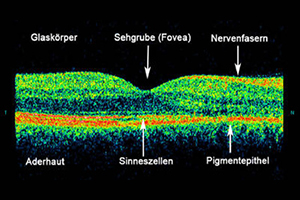

Schwerwiegende Augenerkrankungen wie beispielsweise diabetische Retinopathie, die altersbedingte Makuladegeneration oder das Glaukom kündigen sich häufig durch eine Dickenveränderung der mehrschichtigen Netzhaut an. Einschränkungen des Sehens und merkbare Symptome folgen meist verzögert, wenn das Krankheitsbild bereits fortgeschritten ist. Es ist daher wichtig, dass die Krankheitsbilder in einem möglichst frühen Stadium festgestellt werden.

Mit dem Einsatz der optischen Kohärenztomographie (OCT) gelingt es genaue Informationen über die kleinsten Ebenen im Auge in höchster Qualität und Auflösung zu erhalten. Oft kann diese nicht invasive Methode sogar eine fluoreszenzangiografische Untersuchung ersetzen, bei der ein Farbstoff in die Armvene injiziert wird. Bei manchen unklaren Netzhauterkrankungen, bei denen der Befund einen normalen Augenhintergrund und Fluoreszenzangiographie zeigt, kann erst durch die OCT die richtige Diagnose gestellt werden.

Die Untersuchung am OCT ist ähnlich einem Foto ohne Blitz und dauert nur wenige Minuten. Sie erfolgt absolut schmerzfrei und ohne Berührung der Augen. Die Netzhaut wird in dem untersuchten Bereich durch ein Laserverfahren in optische Schnitte zerlegt und es kann damit wie bei einem mikroskopischen Gewebeschnitt die Netzhaut des Auges beurteilt werden. Die Auflösung der erzeugten Bilder ist ca. 10-mal höher als bei herkömmlichen Ultraschallverfahren am Auge und wesentlich genauer als bei einer Computertomographie (CT) oder einer Magnetresonanztomographie (MRT).

Der optische Schnitt einer normalen Netzhaut

Die untere Abbildung zeigt einen Schnitt durch die Netzhautmitte (Makula) mit der wichtigen Stelle für das Scharfsehen - die Sehgrube (Fovea). Die Einsenkung stellt den Normalbefund dar, welches in der dreidimensionalen Bildgebung besonders gut veranschaulicht wird.

normaler Netzhautbefund - OCT

Optische Kohärenztomographie – OCT